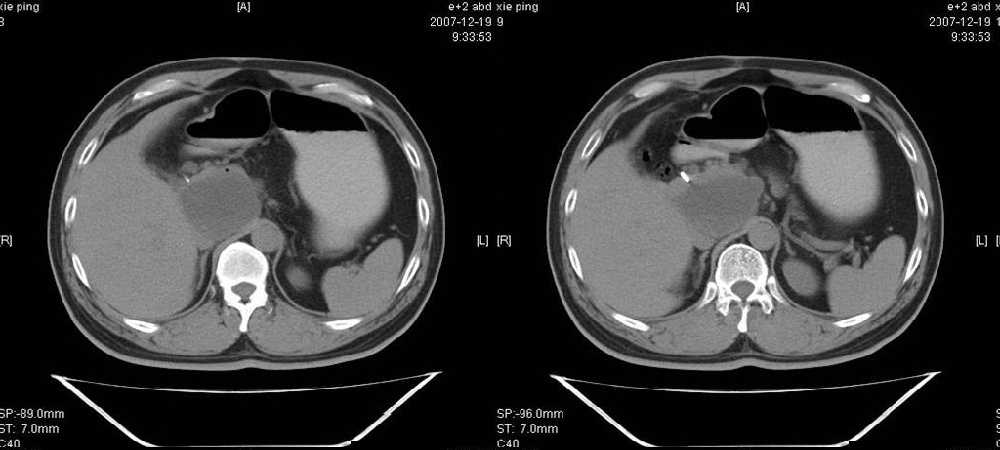

临床病史:患者,男,53岁,因反复上腹部饱胀不适2+月,在餐后或饥饿时明显,伴呃逆,无呕吐、呕血,无腹痛腹泻;2年前腹腔镜胆囊切除,否认肝炎、结核等病史。

pmrc显示病变与12指肠关系密切,与胆系不相通。

餐后或饥饿时明显,考虑12指肠溃疡并穿孔形成假囊肿(外瘘积液包裹),与lc手术无关。

考虑十二指肠憩室。从影像上看,病变位于下腔静脉前胰头后方十二指肠内侧,肝尾叶受压,说明病变来源于后腹膜;胰胆管成像胰管和胆道未见扩张,总胆管中段受压未显示,上下段正常,所以不考虑来源与于肝尾叶和总胆管的囊肿。考虑为十二指肠憩室或小网膜囊肿。

楼上高手,本例的确是一例十二指肠憩室.